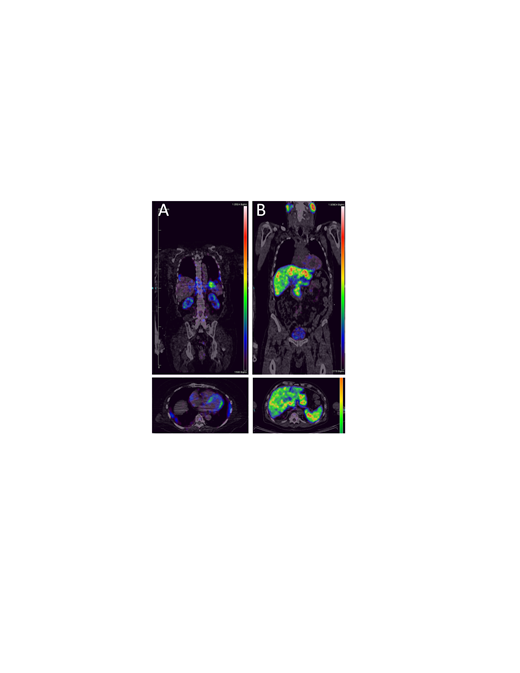

Analysis of PET images indicated retention of 124I-p5+14 in the heart, kidneys, liver, spleen, pancreas, bone marrow, lung, and adrenal gland of AL patients (Fig. 1 (A) Cardio-renal AL, and (B) Hepatosplenic AL amyloidosis). Cardiac uptake of the radiotracer was observed in 80% of AL patients (n = 5) who received ≥ 1 mCi 124I-p5+14, with a mean myocardium:blood pool ratio of 2.3 ± 0.5 in positive images. Additionally, liver, spleen and kidney retention of 124I-p5+14 was observed in 20%, 40%, and 60% of AL patients, respectively. Furthermore, retention of the radiotracer has been indicated in the heart, spleen and kidney in patients with ATTR and ALECT2--associated amyloidoses.